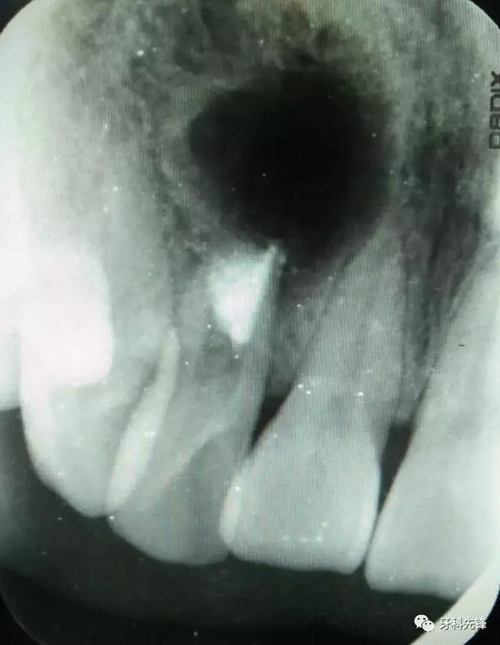

圖1.術前的根尖片影像檢查:12根管粗大、根尖未形成。根尖下方有一橢圓形囊腔,囊內(nèi)有牙。